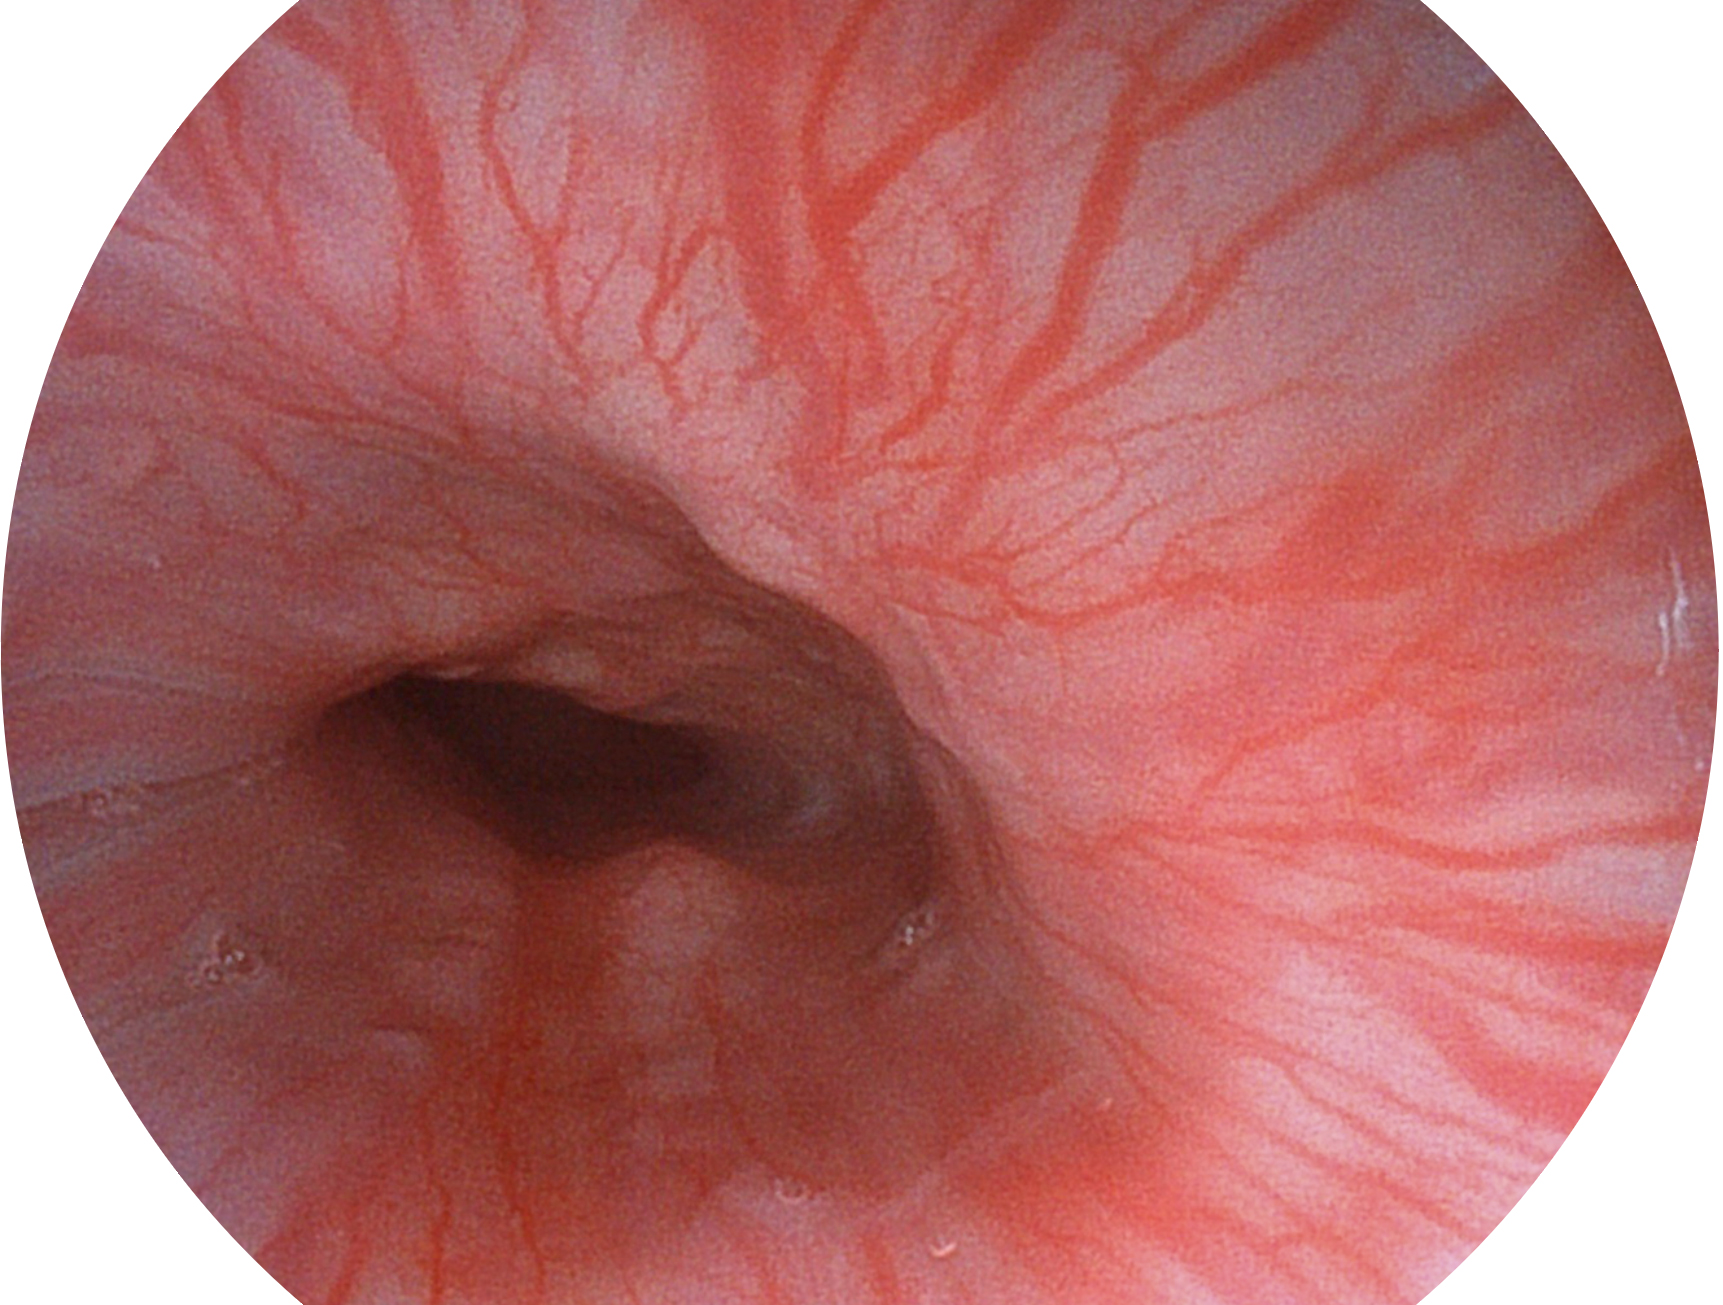

狗万官方网站新开发的内镜染色技术,主要是基于多波长LED 光源的开发,VLS-55Q 四波长LED 光源是由四个不同颜色的LED光按照相应照明模式所规定的特定发光比例进行合束后形成,合束后形成的照明光的光谱由红光、绿光、蓝光及蓝紫光这四个不同的波段范围构成。具有更高光谱自由度,通过光谱比例的控制,实现了聚谱成像技术,英文全称为“Spectral Focused Imaging, SFI”,缩写为“SFI”和光电复合染色成像技术,英文全称为“Versatile Intelligent Staining Technology, VIST”,缩写为“VIST”。